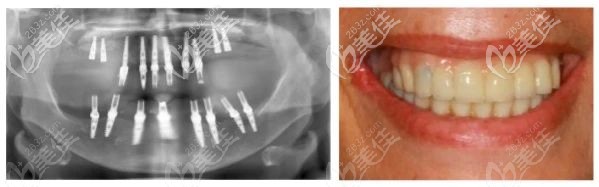

為了幫助老人實現(xiàn)即刻負(fù)重,在下頜拔牙后使用去骨導(dǎo)板修整牙槽嵴,然后在種植3D導(dǎo)板的引導(dǎo)下植入了8枚種植體。

由于是全口種植牙,上下咬合關(guān)系需要準(zhǔn)確設(shè)計,取模并制作臨時牙冠,難度比單顆種植牙修復(fù)大。

種植手術(shù)后,拍攝全景片,老人戴臨時牙冠,達(dá)到了即刻負(fù)重的效果。

術(shù)后6個月后,殷龍醫(yī)生選擇了鈦支架結(jié)合氧化鋯的復(fù)合修復(fù)方式進(jìn)行修復(fù),老人牙齒獲得良好的美學(xué)效果。而且X光片顯示種植體骨結(jié)合也比較好。